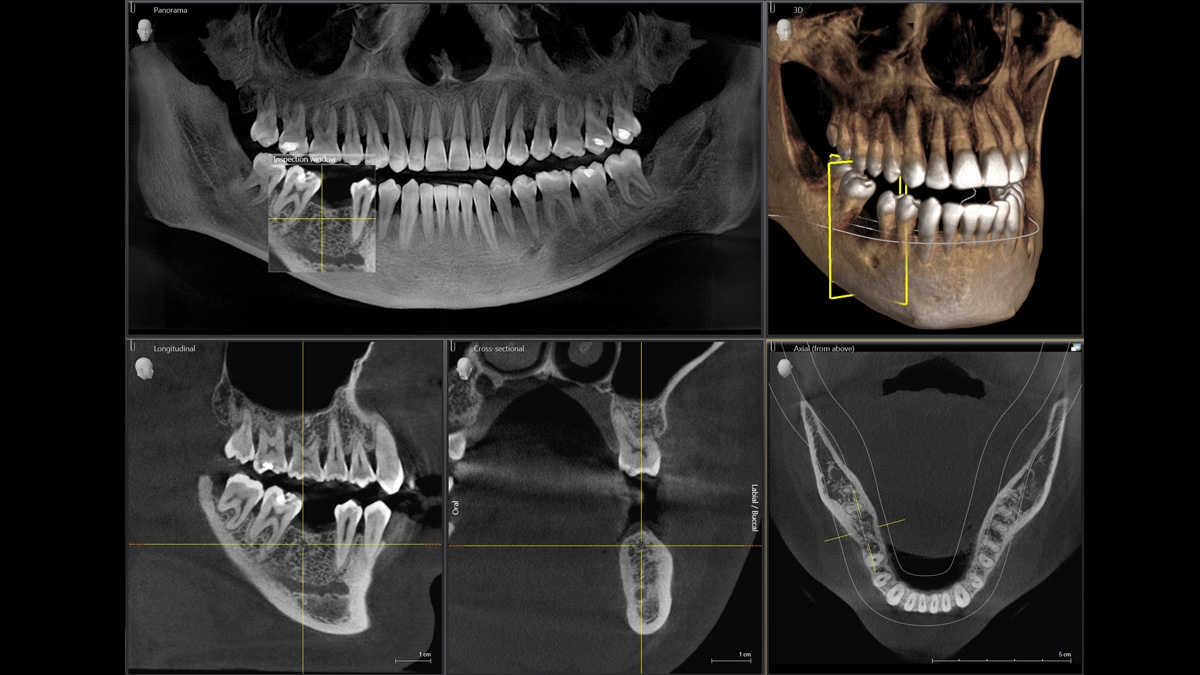

Диагностика последнего поколения, идеально решающая задачи рентгеновского обследования независимо от размеров клиники. Поля изображения зависят от определенной клинической картины, поэтому специалистам так удобно работать с ORTHOPHOS SL 3D. Данная установка делает объёмные картинки для одиночной реставрации в 3D качестве полностью всей челюсти такого размера, которого требуется.

Планирование одиночной реставрации, эндодонтические исследования и пр. – для этого специалист может выбрать объёмные варианты 8 х 8 см или 11 х 10 см, также предлагается объём 5 х 5,5 см. Снимки в HD-качестве, стандартные настройки или выбор объёма обследования в зависимости от диагноза — всё это врач получает в отличном качестве, а для пациента излучение в районе исследования минимально.

С технологией SL можно за один сеанс получить огромное количество снимков. Те из них, где фокусировка наиболее чёткая, автоматически соединяются. В итоге одна процедура — снимки челюсти полностью в самом лучшем качестве. Даже нестандартные случаи не станут помехой в обследовании. К примеру, при ретинированных зубах уже после того, как снимок сделан, нужную область можно выделить подробнее, и в ещё одном рентгене необходимость отпадает.